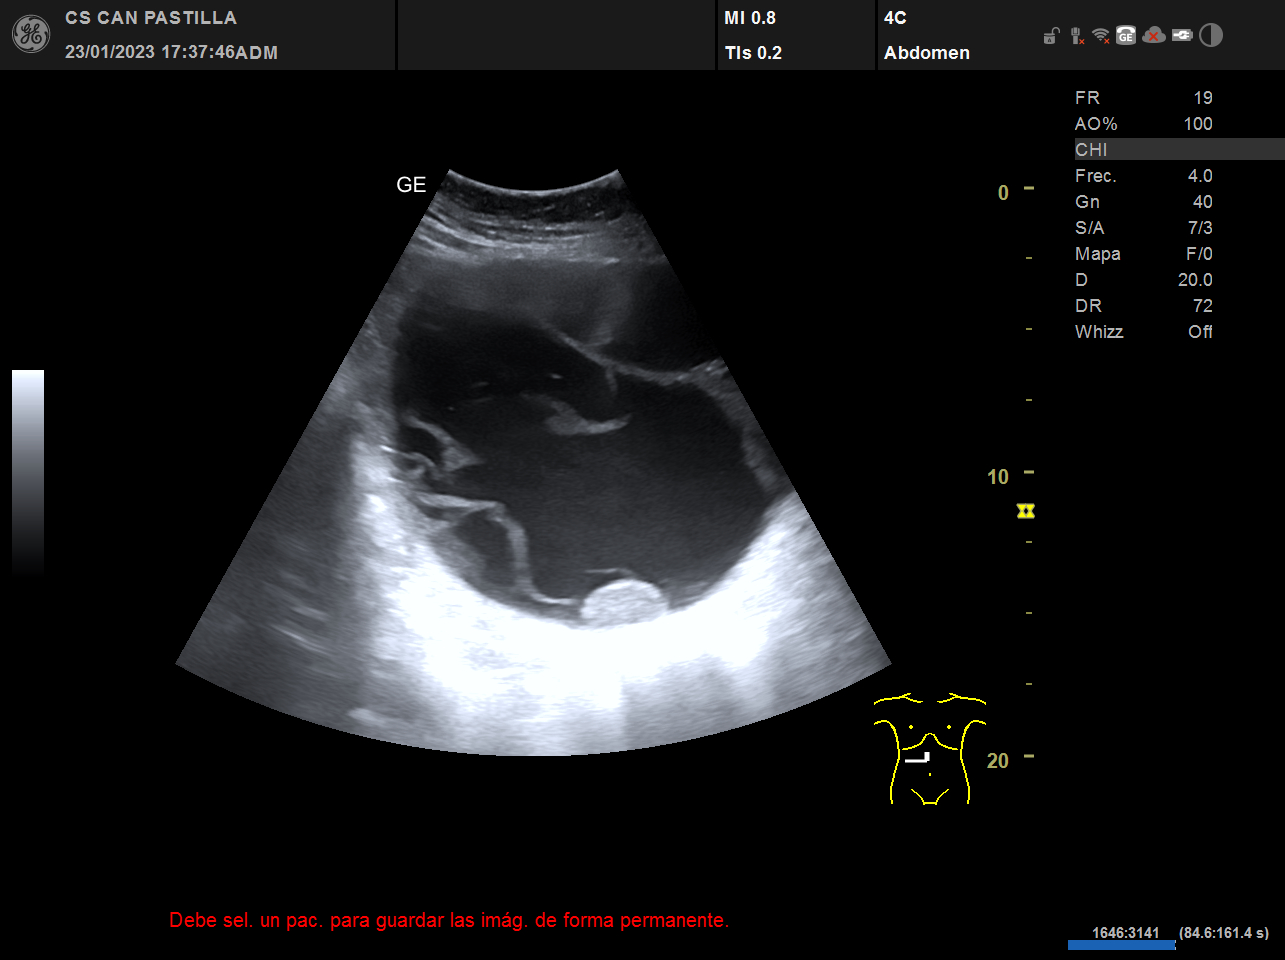

ECO abdominal: destacan imágenes anecóicas con refuerzo acústico posterior y septos en su interior, sugestivas de quistes complejos de gran tamaño (el mayor de ellos de 15 cm de diametro) o un solo quiste tabicado de gran tamaño. Dificultad para observar el parénquima hepático de forma completa, dados la ocupación de las imágenes quísticas.